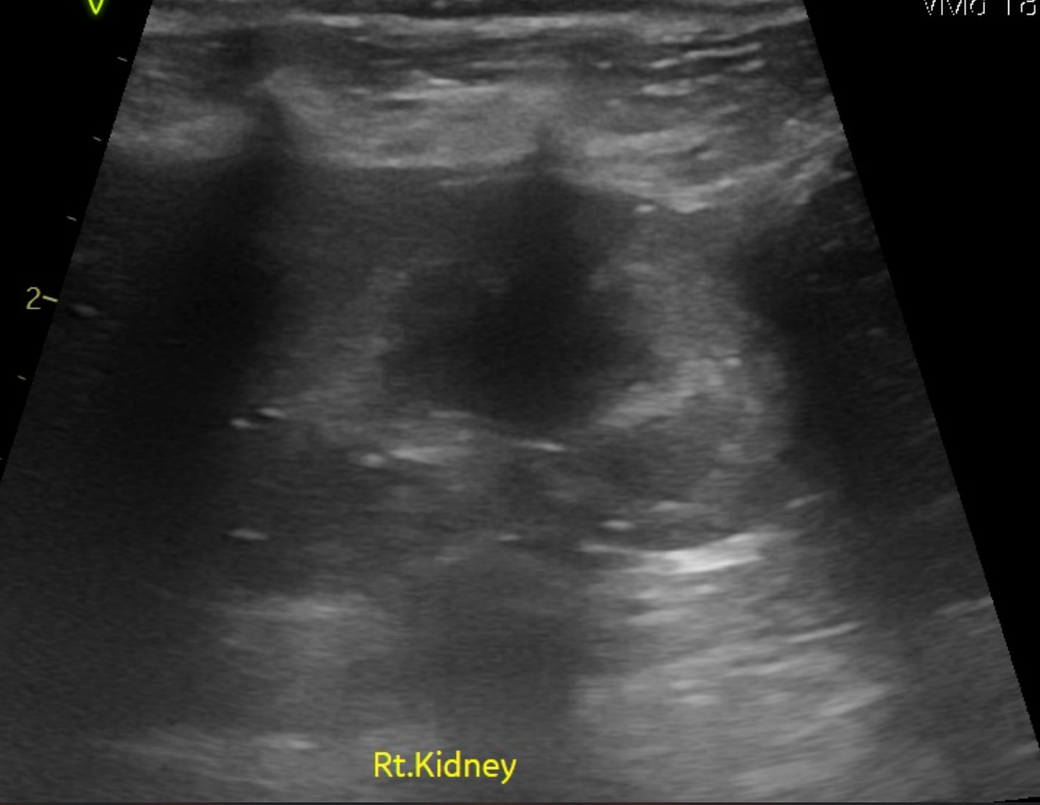

강아지 신장결석 종류 모양만으로는 판단이 안되나요? 소변에선 크리스탈이 발견된게 없다고 합니다

모양만으로 추측 조차 할수가 없는건가요? 한번 봐주시면 감사하겠습니다.

예, 없습니다. 결석이 매우 커진 상태 (몇센치미터 크기 정도)로 커졌을때나 일부 추정되지만 겉면과 내부 코어의 씨앗의 성분은 별도라 이때는 또 성분검사를 해야 하는정도로 부정확합니다.